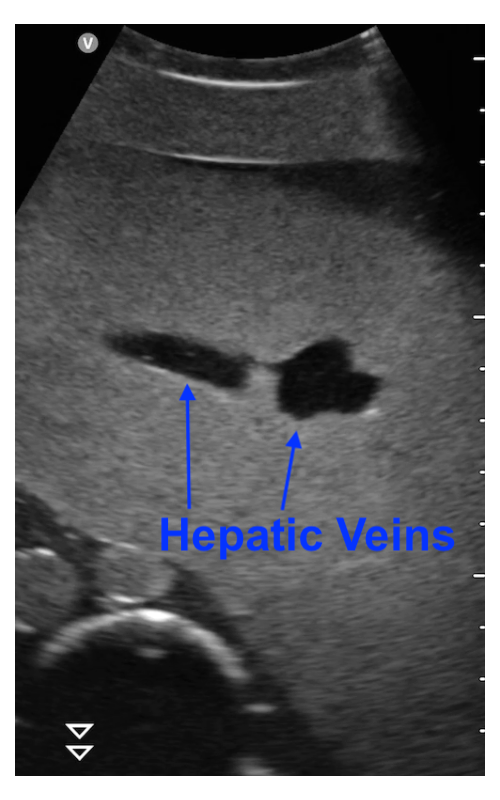

The HV is arguably the most important image feature in our US imaging pipeline. We use HV in liver ultrasound images as the key landmark to navigate the US probe on the body, and most importantly, determine the the CT-physical coordinate mapping Tcpsuperscriptsubscript𝑇𝑐𝑝{}^{p}T_{c}start_FLOATSUPERSCRIPT italic_p end_FLOATSUPERSCRIPT italic_T start_POSTSUBSCRIPT italic_c end_POSTSUBSCRIPT. The HV is a group of major blood vessels in liver that originate from multiple liver sections and ultimately join the inferior vena cava. These vessels are easily distinguishable in various perspectives of CT and ultrasound images. In particular, the first branching point of the upper hepatic veins exhibits an iconic ‘bunny ear’ shape in axial ultrasound images as shown in Fig. 5(b). Literature on US-CT registration has demonstrated great success using HV as the feature for registration[30, 29].

We train two segmentation networks with the U-Net architecture[31] to identify HV in axial-view US images. One is the full-vessel model, which segments the entire system of HV vessels. The full-vessel model is needed for 3D HV model acquisition and final target imaging(Sections IV-D and IV-F). The other is the branching point model, which segments only the HV vessels along the middle hepatic vein, near the first branching point of upper hepatic veins. The branching point model is only used to find and centralize the HV branching point in the US probe’s field of view(Section IV-C). Figure 6 illustrates the expected segmentation from these two models.